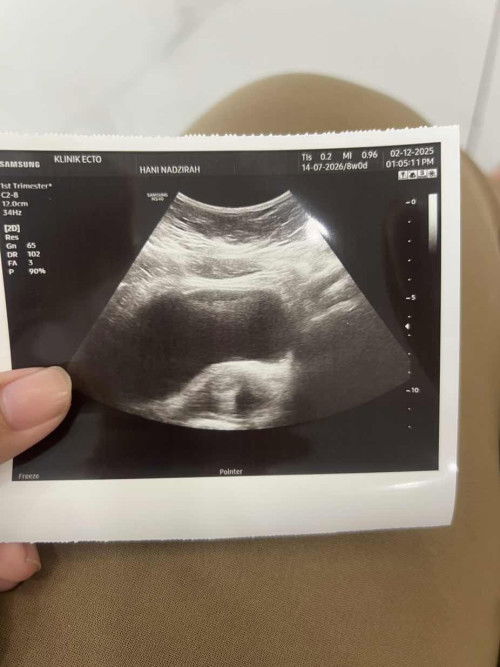

nak tanya yg ni kantung kee pergi klinik doc pon tk tahu tu kantung ke bukan huhu janin tk clear hm.

Nampak Dari gambar tersebut doktor awak buat scan transabdominal (Dari luar). Jika kandungan masih awal (less than 8 weeks) susah nak nampak kantung dari scan luar sbb masih kecil. Selalunya buat TVS (transvaginal ultrasound) baru nampak. Jika x da symptoms seperti sakit segugut atau pendarahan selalunya doktor akan nasihat utk kembali 2 minggu lagi repeat scan. Boleh Cuba pergi klinik yg ada offer TVS, atau tunggu lagi seminggu/dua. Good luck sis.

Baca laginampak mcm ada kantung tapi janin takde nampak lagi. mcm sy pergi scan awal cuma nampak kantung lepastu repeat lagi 3 minggu pergi scan Alhamdulillah dh boleh nampak baby 🥰 semoga dipermudahkan urusan awk 🥰